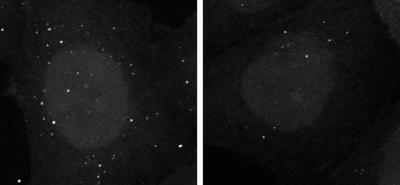

Autophagy serves to clear a variety of toxic waste from cells, including misfolded proteins and defective mitochondria. These two types of cellular trash accumulate in neurons from Parkinson's patients, suggesting that autophagy could be impaired in these cells. A commonly amassed protein in Parkinson's disease is alpha-synuclein, whose gene is often mutated or overexpressed in familial forms of the illness. David Rubinsztein and researchers from the University of Cambridge in England found that excess alpha-synuclein inhibits autophagy by blocking formation of the autophagosome—the double-membraned vesicle that engulfs cytoplasmic garbage and delivers it to lysosomes for destruction.

Previous research revealed that alpha-synuclein inhibits Rab1a, a small GTPase that controls secretory transport from the Endoplasmic Reticulum to the Golgi. Rubinsztein and colleagues now provide new insight into the role Rab1a plays in autophagy, and why blocking it has such dire consequences. The team found that lack of Rab1a impaired autophagosome formation, whereas an abundance of the GTPase reversed the inhibitory effects of alpha-synuclein on autophagy. Rab1a and alpha-synuclein act specifically at an early stage of autophagosome formation: an abundance of alpha-synuclein or lack of Rab1a disrupted an early acting part of the autophagy machinery called Atg9 and blocked the formation of autophagosome precursors known as omegasomes.

Alpha-synuclein's blockade of autophagy could enhance the gradual accumulation of toxic proteins and dysfunctional mitochondria, sensitizing neurons to cell death.